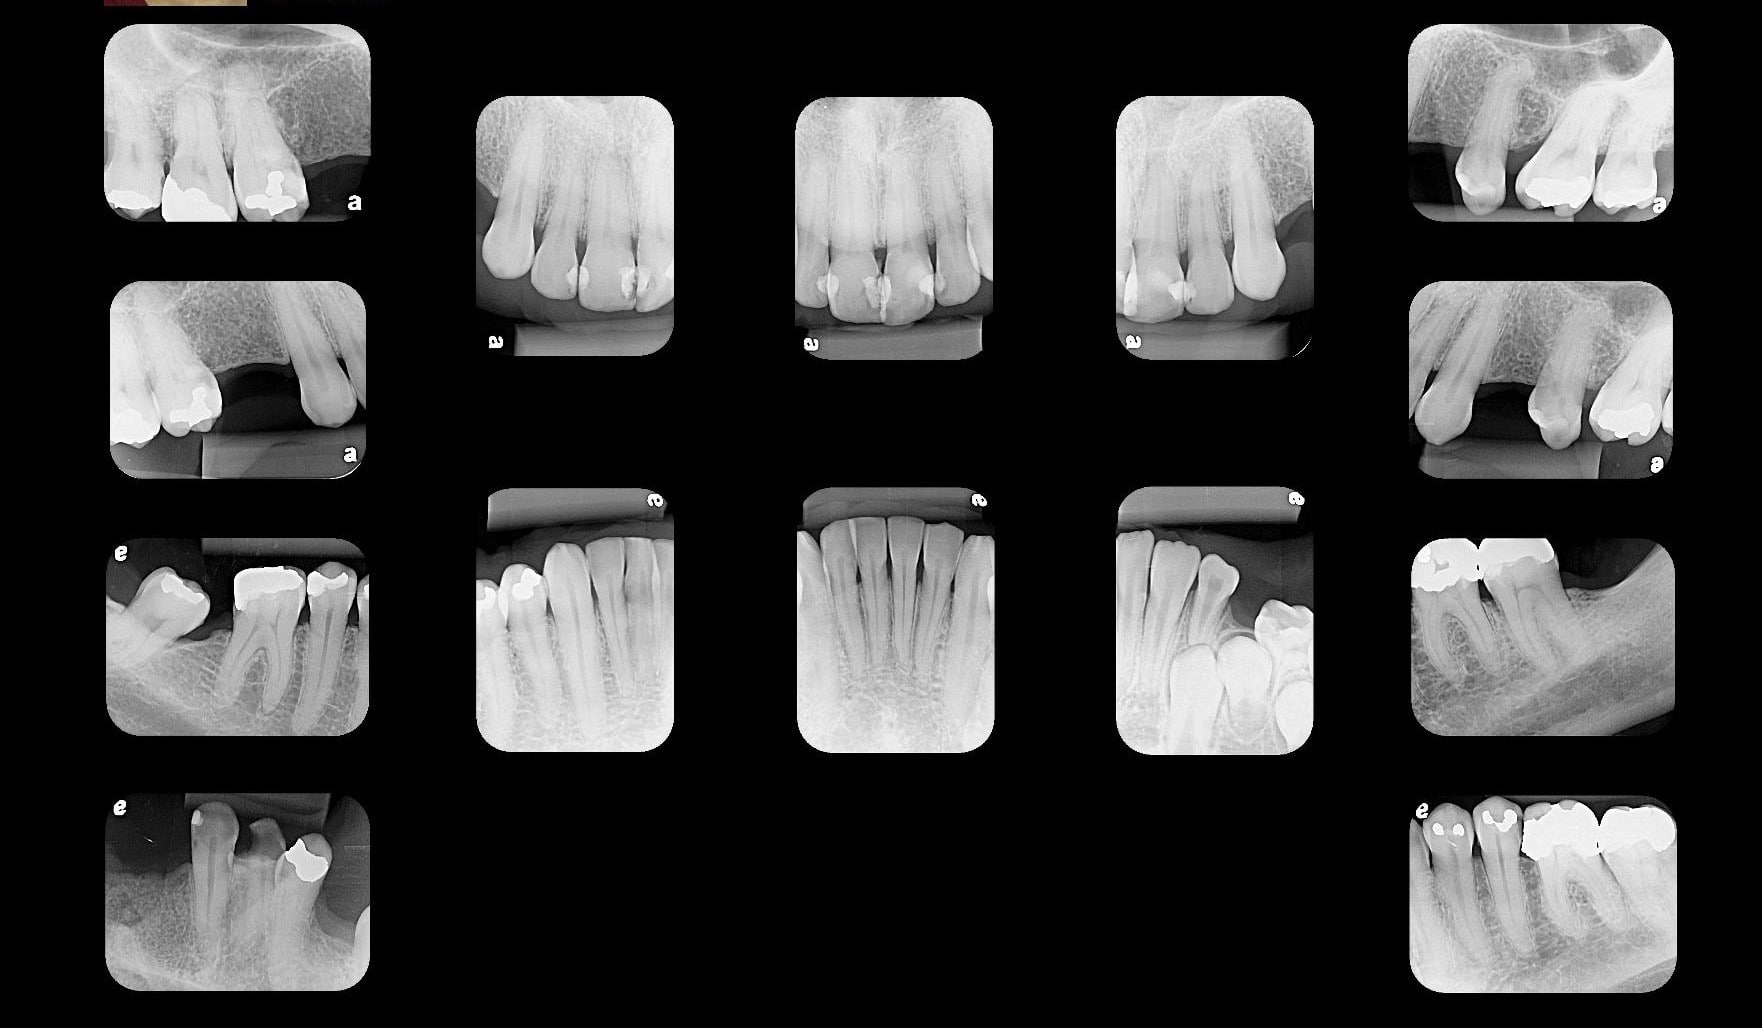

Periapicais

Interproximais

Levantamento Periapical